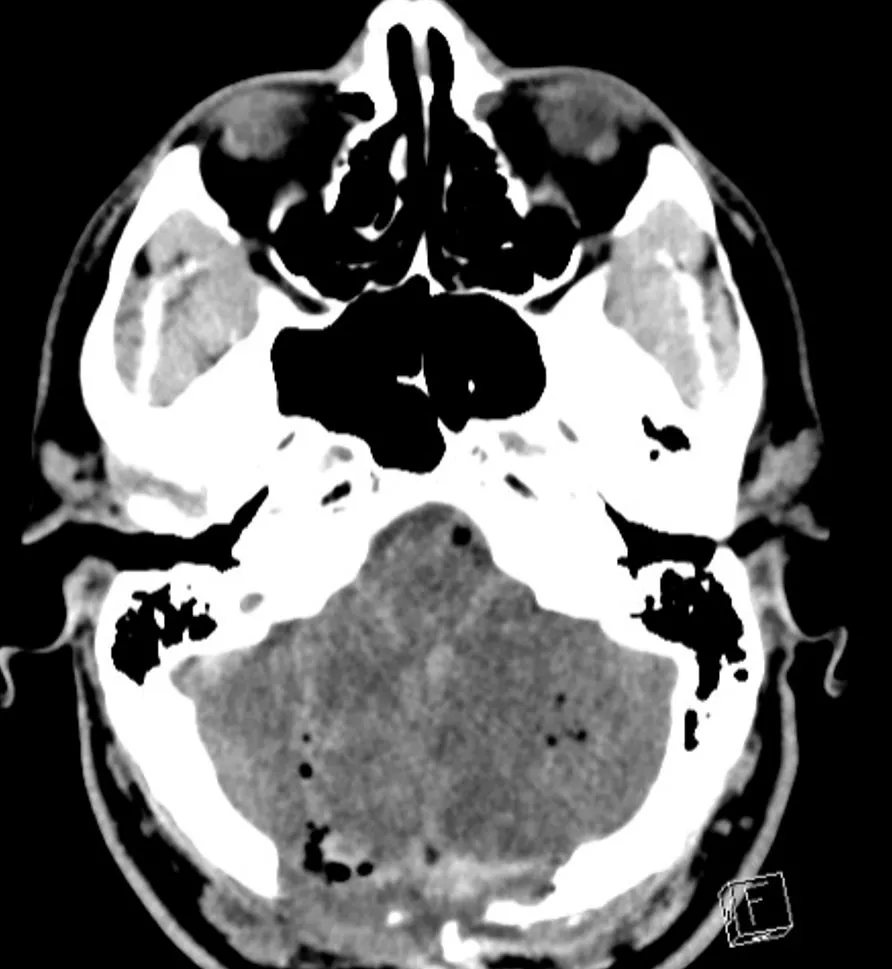

Approximately 12 hours after admission, the patient experienced a decline in his mental status, prompting a stat non-contrast computed tomography (CT) of the head which revealed bilateral cerebellar strokes. The associated cytotoxic edema resulted in significant mass effect on the 4th ventricle and early hydrocephalus.

The patient was then taken to surgery for an emergency sub-occipital decompressive craniotomy and placement of an extra ventricular drain to relieve the pressure.